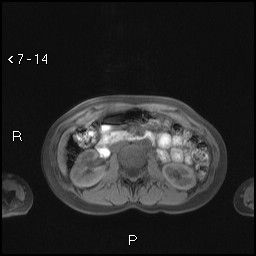

Aspetti RM: piccolo nodulo dell’istmo pancreatico ipointenso in T2.